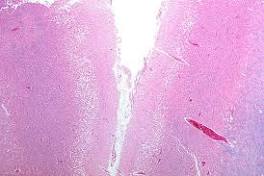

The beauty of CANCER: Researchers reveal 3D models of tumours In cancer cells, however, approximately 5 percent are what scientists call 'driver' mutations - changes that allow cells to divide faster or live longer.